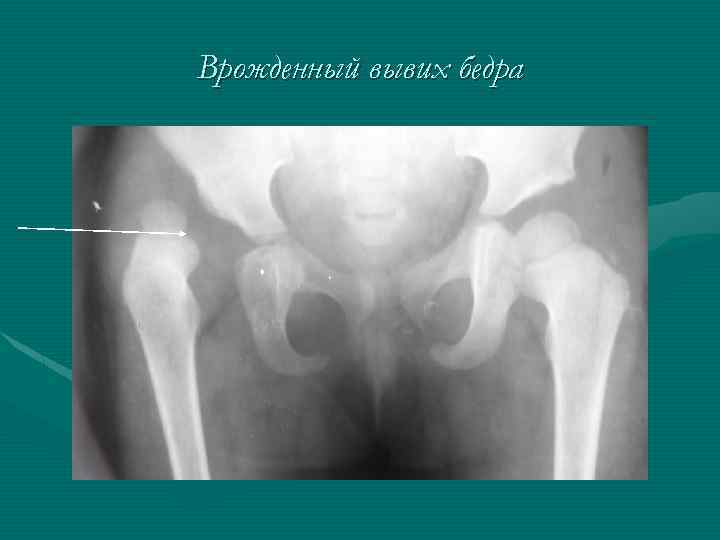

Врожденный вывих бедра. Он встречается у 0, 2 -0, 5% всех новорожденных, причем у девочек в 4 -7 раз чаще. При остаточной (резидуальной) дисплазии вертлужная впадина недоразвита, но головка бедра стоит правильно. У больных врожденной дисплазией головка бедра занимает эксцентрическое положение, создается врожденный подвывих, а затем развивается врожденный вывих. Если нет ядер окостенения, вертикальная линия, проходящая через верхненаружный выступ вертлужной впадины, пересекает внутренний край так называемого клюва бедра, который отстоит от седалищной кости больше, чем на здоровой стороне. Показатель вертлужной впадины (ацетабулярный индекс) доходит до 35 -40 градусов. Характерны уступообразная линия Менард-Шентона и прерывистая линия Кальве. Расстояние от наиболее выступающей проксимальной поверхности бедра до линии Хильгенрайнера (ацетабулярная линия, соединяющая оба У-образных хряща) меньше 1 см. Горизонталь, проведенная по нижнему краю шейки бедра, проходит выше так называемой "слезинки", или запятой Альбана-Келлера. Если же у больного уже образовались ядра окостенения, кроме этих симптомов выявляются следующие: линия Хильгенрайнера пересекает головку или проходит выше ее. Окостенения на стороне вывиха задерживается и точка окостенения головки меньше, чем на здоровой стороне, атрофируются кости, деформируется головка, укорачивается и утолщается шейка бедра, развивается антеторсия шейки.

Врожденный вывих бедра